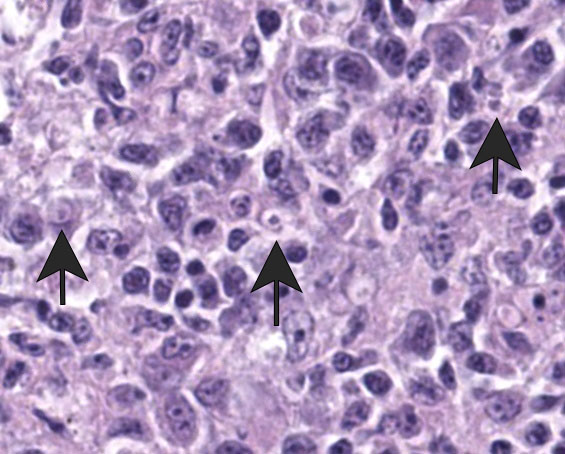

Liver: Surrounding portal regions and occasionally coalescing are infiltrates of moderate numbers of lymphocytes and histiocytes that disrupt the hepatic architecture. Within the lymphocytes and histiocytes are numerous, 2 um in diameter, basophilic protozoal organisms surrounded by a thin, clear halo that peripheralizes the nucleus. The inflammatory cells separate and individualize the hepatocytes, which display mild karyomegaly and frequent binucleation. Free within the sinusoidal lumina and within portal and central veins are numerous, approximately 5 um diameter, pyriform flagellate protozoa with a single, variably distinct nucleus. Occasional large lymphocytes and rare plasma cells circulate throughout the sinusoids.

Systemic isosporosis was identified histologically and cytologically in histiocytes and lymphocytes of an inflammatory response affecting small intestine, liver, spleen, and other tissues. Isosporosis is well-described in captive and free-range passerines. Formerly known as atoxoplasmosis, the pathogenesis of systemic isosporosis remains uncertain but involves extraintestinal invasion of mononuclear cells by sporozoites that undergo asexual reproduction. It is endemic in populations of passerines with fatal infections associated with stress, concurrent infections, or immunosuppression.3 Mortality due to Isosporasp in wild birds is low, however, mortality in captive birds is significantly higher. Stress due to captivity and increased shedding of infective oocysts have been proposed as possible causes for the higher mortality observed in captive passerines.3 As seen in this case, isosporosis is most commonly seen in the proximal segments of the small intestine and is accompanied by infiltration by mononuclear cells. Compromise to the intestinal mucosa as a result of the severe inflammation in this case could have led to invasion by the second protozoal infection.

Many thanks to this contributor for an interesting case and well-written comment! It has been a while since the WSC saw a case of atoxoplasmosis (WSC 2009, Conf 18, Case 3), and this case provided some excellent discussion points. This was a challenging slide for many participants due to the lymphoproliferative nature of this protozoal infection, which, depending on the severity of the infection and the species affected, can be confused with lymphoma caused by gallid herpesvirus-2 (Marek?s disease), and avian retrovirus (lymphoid leukosis), etc.3 This was true in this conference, and some participants wondered about a lymphoma as the primary disease with the protozoa being secondary. The Isosporaserini were easier for the participants to find in this collection of tissue, but finding the flagellates, (Cochlosoma anatis) proved more difficult on the Hand E section (however, once the first flagellate were identified, participants were able to find them with ease.) Flagellates have a small, pinpoint nucleus and piriform shape, which differentiates them from mucin and debris. The group decided that there was not definitive evidence of cryptosporidia on the section of bursa, but only a very limited area of bursal epithelium (which cryptosporidia invade) was present in the section, so sampling was extremely limited.

Finally, Dr. Pesavento quizzed participants on the ultrastructural images from this case, which was an appreciated, succinct review for many attendees. Key takeaways from this discussion included trusting your anchors (i.e. erythrocytes, nuclei, etc.), determining the number of cell profiles in the EM image, and knowing what normal looks like so you can evaluate the abnormal. The protozoal organisms on EM had some key characteristics to look for, as well, including the flagella on the Trichomonads with their classic microtubule 9+2 arrangement, and the apicomplexan conoid, rhoptries, and micronemes within the Isospora.5,6 Her last piece of wisdom in this case regarded microvilli on EM: don't call them microvilli unless you can see the actin microfilaments holding them up. If not, they are termed "cellular projections."